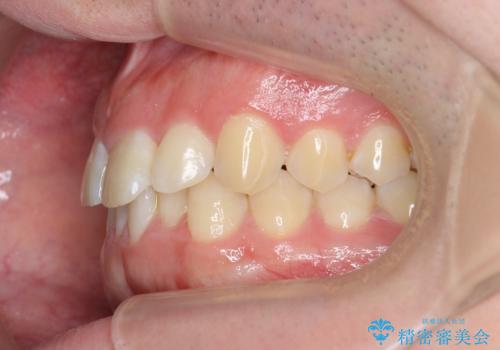

前歯が隠れていて見えない クロスバイトの矯正治療

- 「前歯が1本隠れていて見えない、歯並びを矯正治療で改善したい。」と希望され来院されました。

奥に隠れている前歯を並べられるスペースを確保したのち、歯並びを整えていきます。

前歯のスペース不足により1本だけ後方に位置している状態でしたが、しっかりとスペースを確保し配列することができました。